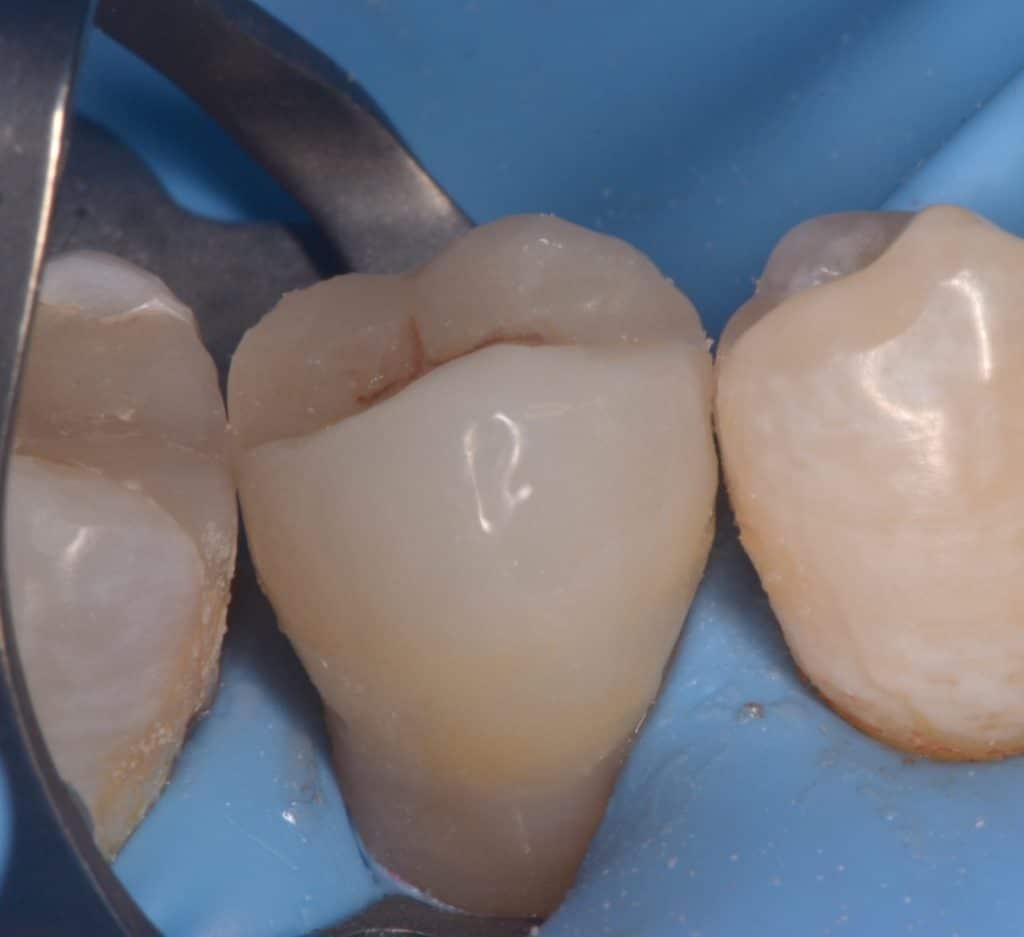

Immediate after DME , gold standard clearfil SE bond used, RC with flowable composite from GC, Ribbond and ever x flow covered by composite for core building

2 weeks later , preparation, macro-core build up

Buccal view